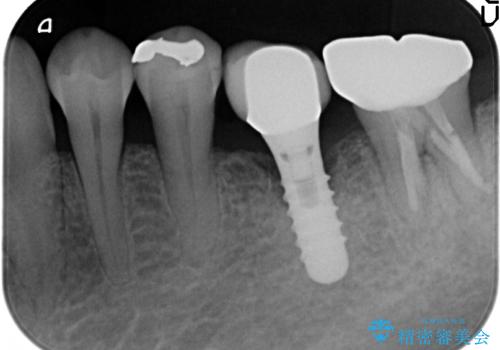

- 左下5番目の銀歯が気になるのでセラミックにしたいといらっしゃった方の症例です。

銀歯及び虫歯を除去後、セラミックインレーによる修復を行いました。